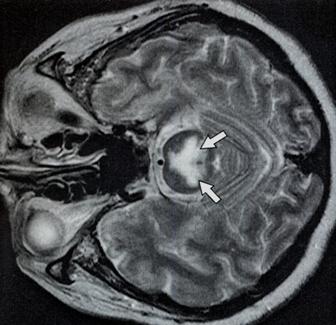

ADAPTACIÓN CEREBRAL A LA HIPOTONICIDAD

Figura 4 y 5

La disminución en la osmolaridad extracelular, causa

un movimiento del agua dentro de las células,

incrementando el volumen intracelular y causando

edema tisular. Esto mismo ocurre a nivel cerebral,

con aumento de la presión intracraneal. En la etapa

temprana de la hiponatremia (una a tres horas), el

volumen extracelular corporal total disminuye, por

el pasaje de líquido dentro del sistema nervioso

central, lo que es shunteado hacia la circulación

sistémica. El cerebro se adapta, por pérdida de

potasio celular y de solutos orgánicos, lo que

tiende a disminuir la osmolaridad, sin una ganancia

sustancial de agua. Si la hiponatremia persiste,

otras sustancias osmóticas como la fosfocreatina

myoinositol, aminoácidos (glutamina y taurina) se

pierden, disminuyendo de esta manera el edema

cerebral. En los pacientes donde falla esta

respuesta adaptativa, se desarrolla edema cerebral,

cuando comienza la hiponatremia. Los que tiene una

buena respuesta adaptativa también pueden sufrir el

síndrome de desmielinización, si la hiponatremia es

corregida rápidamente, o si es muy severa. Algunos

pacientes, como mujeres menstruantes, psiquiátricos,

con polidipsia, con diuréticos tiazídicos, tienen

mayor riesgo, de desarrollar lesiones neurológicas.